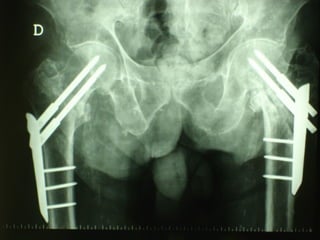

La lesione dell’apparato muscolo scheletrico che richiede  in ogni caso  un trattamento chirurgico con  priorità   assoluta  è la rottura dell’anello pelvico , che comporta una emorragia severa nel retro peritoneo e nella cavità peritoneale.

Immediata riduzione e fissazione del bacino

Se la risposta emodinamica a questo trattamento è buona il paziente verrà monitorato e potrà essere programmato un successivo intervento di osteosintesi definitiva

Angiografia e/o packing pelvico Se il paziente rimane instabile